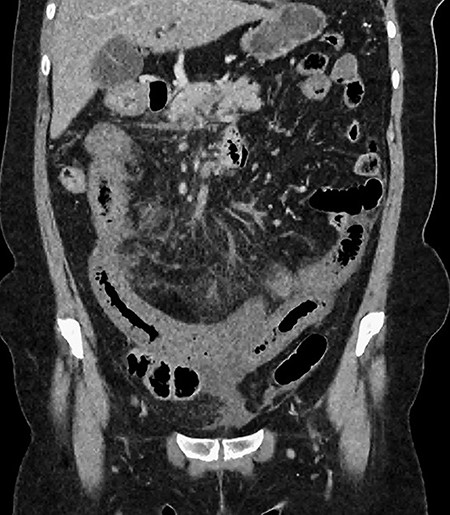

A 61-year-old female presented to a regional hospital with a 3-week history of intermittent diarrhoea, vomiting and generalized abdominal pain. She had a diffusely tender abdomen but was not peritonitic, and was shocked with a heart rate of 110 beats per minute, blood pressure of 89/45 mmHg and was peripherally cool. Her blood tests revealed a lactate of 7.2 mmol/L, which worsened to 7.8 mmol/L during resuscitation with intravenous fluids, and white cell count was 30.9 × 109/L, with an international normalized ratio (INR) of 1.4. She had an acute kidney injury with a creatinine of 119μmol/L and estimated glomerular filtration rate (eGFR) of 43 mL/min/1.73m2. Computed tomography (CT) revealed extensive thickened loops of non-enhancing small bowel with pneumatosis, moderate free fluid and a large splenic infarction. There was extensive thrombosis of the splenic vein and superior mesenteric vein extending into the portal vein to the level of the porta hepatis. Her background history included factor V Leiden and protein S deficiency, for which she had been non-compliant with warfarin during this illness. She had no surgical history (Figs. 1–5).

CT showing multiple thick-walled, non-enhancing loops of small bowel.